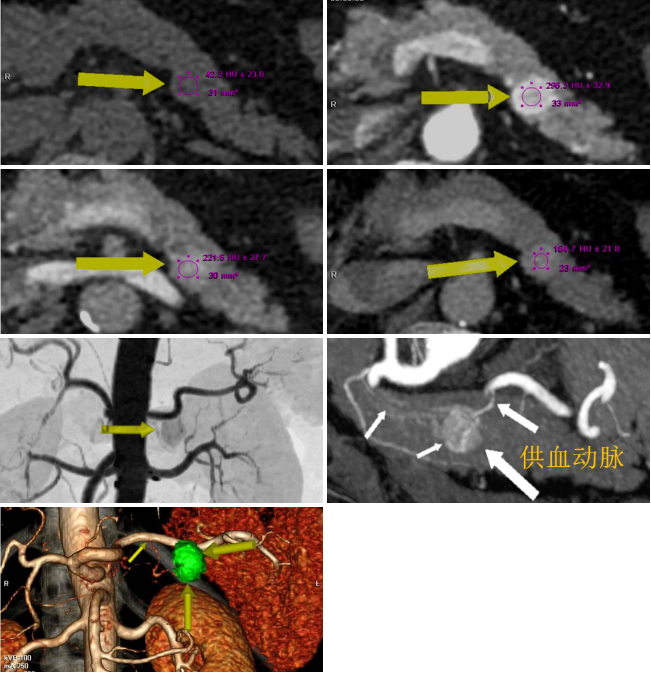

病例一 女,71歲,反復(fù)發(fā)作心慌、 胸悶、 出汗,血糖2 . 56 mmol/ L。

免疫組化:

CEA(-),CD31:血管內(nèi)皮細(xì)胞(+),Ki67:約1%瘤細(xì)胞陽(yáng)性,CK8(+),CK19(+),S yn(+),CgA(+)。

動(dòng)脈期可見(jiàn)胰腺體尾部腫瘤明顯強(qiáng)化,CT-MIP圖可見(jiàn)供腫瘤血血管,VR圖像可清晰顯示腫瘤的供血血管以及與周圍組織的關(guān)系。 術(shù)后結(jié)果為胰腺體尾部胰島素瘤。

病例二 女,63歲,以持續(xù)性腹部疼痛不適半天就診。既往有冠心病15年、心房纖顫史5年余;高血壓5年。

采用心臟+主動(dòng)脈血管一站式檢查,可見(jiàn)該患者腸系膜上動(dòng)脈及其分支充盈缺損,同時(shí)顯示左心耳內(nèi)多發(fā)血栓, 隨時(shí)有血栓脫落的危險(xiǎn)。

全麻下行剖腹探查、 腸系膜上動(dòng)脈血栓取出術(shù), 病理顯示血栓樣組織機(jī)化。

患者術(shù)后第三天,由于右側(cè)肢體活動(dòng)障礙,語(yǔ)言受限,急查CT發(fā)現(xiàn)多發(fā)腔隙性腦梗塞,MRI檢查后明確左側(cè)急性梗死。

腸系膜上動(dòng)脈栓塞栓子多來(lái)源于心臟,也可來(lái)自于主動(dòng)脈壁粥樣硬化斑塊脫落。腸系膜上動(dòng)脈從腹主動(dòng)脈分出,主干口徑又較大,脫落的栓子易于進(jìn)入,在血管狹窄或分叉處導(dǎo)致血管栓塞。

臨床表現(xiàn)主要有“Bergan三聯(lián)征”1 、劇烈而沒(méi)有相應(yīng)體征的腹痛。2器質(zhì)性心臟病和并發(fā)心房纖顫的心臟病。3、胃腸排空障礙表現(xiàn)如腹瀉、 血便。

640層寬體探測(cè)器CT掃描速度快,可進(jìn)行大范圍心血管一站式檢查,快速排除血管病變,且由于探測(cè)機(jī)單元只有0.5mm,對(duì)于一些微小的病變也能清晰顯示。

病例三 男,54歲,10小時(shí)前無(wú)明顯誘因突然出現(xiàn)右側(cè)胸背部疼痛,呈脹痛,伴有大汗、頭暈癥狀。

腹盆腔CT腸道充氣成像可見(jiàn)橫結(jié)腸脾曲結(jié)腸癌, 升結(jié)腸及降結(jié)腸多發(fā)息肉

腹腔鏡見(jiàn)腹腔粘連較重, 轉(zhuǎn)開(kāi)腹手術(shù), 取左側(cè)腹直肌切口, 逐層進(jìn)腹, 于橫結(jié)腸脾曲觸 及一腫塊, 遂行左半結(jié)腸切除術(shù)。

640層寬體探測(cè)器CT掃描速度快, 掃描時(shí)間只用了2 . 3 s,克服了胃腸道蠕動(dòng)造成的偽影 和漏層, 使腹部圖像質(zhì)量大大提高。 仿真內(nèi)窺鏡的圖像可觀察到黏膜的皺襞 , 不僅可清晰的 顯示小息肉及病變 , 而且可顯示出胃腸道造影及內(nèi)窺鏡易于遺漏的部位。